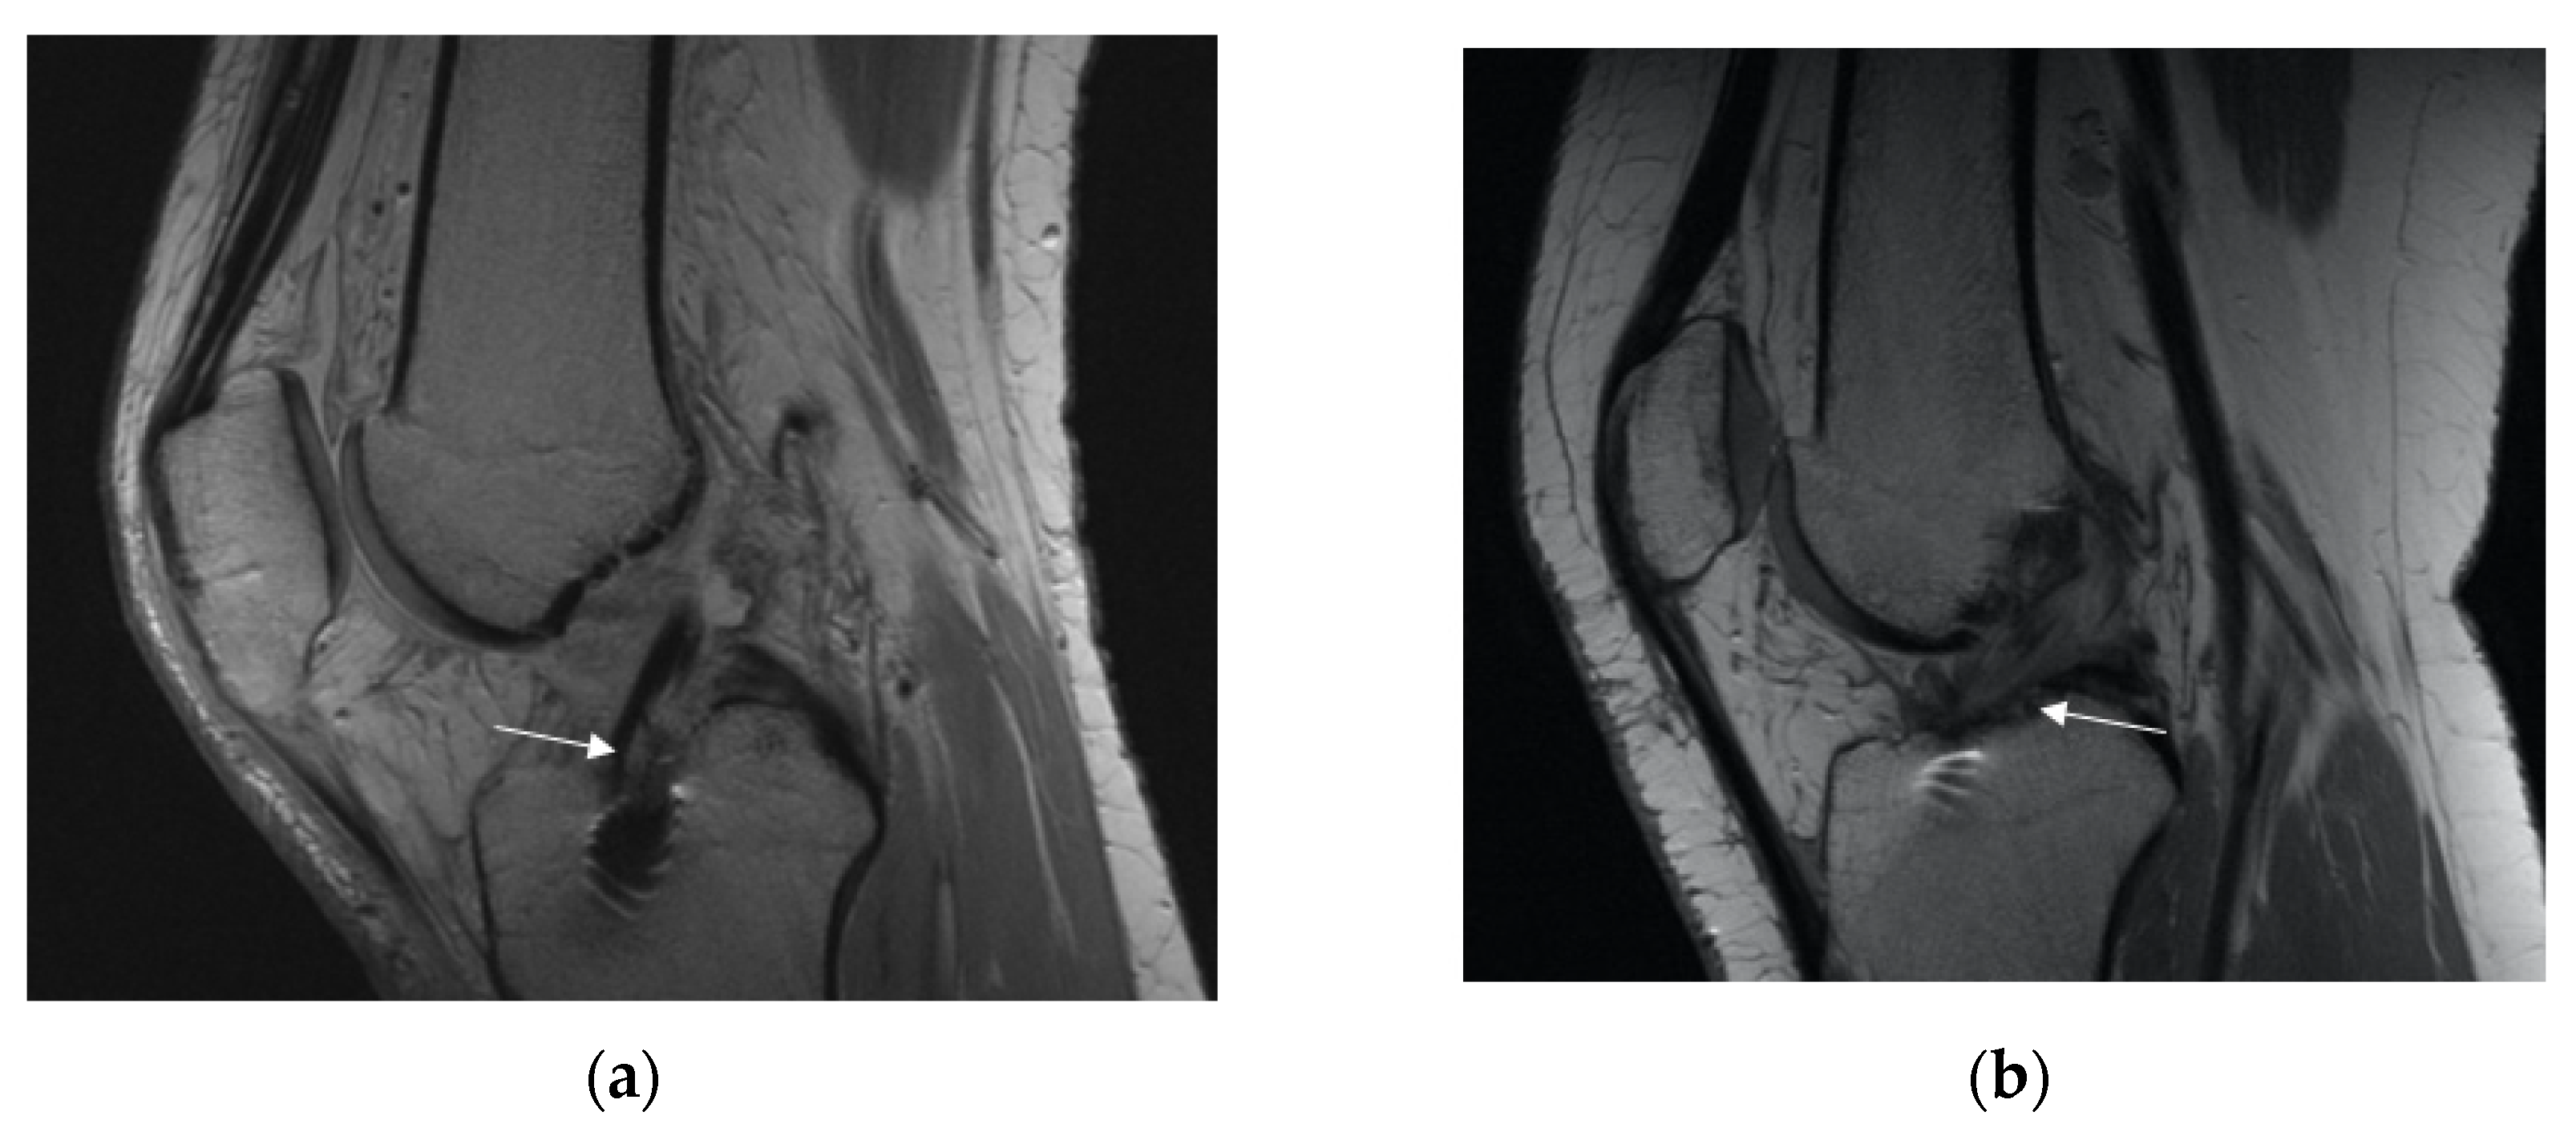

3.2.2. Posterior Cruciate Ligament (PCL) Buckling (Subluxation)

3.2.3. Anterior Tibia Subluxation